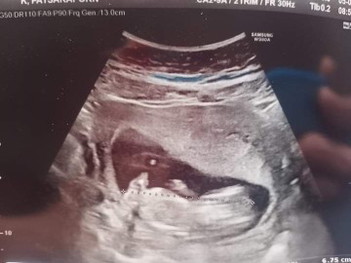

รบกวนสอบถามผุ้รุ้คะ อยากทราบว่าแบบนี้ ญ.รึ ช.คะ แม่บ้านนี้29วีคแล้วยังไม่รุ้เพศเลยคะ

อยากทราบว่าแบบนี้ ผุ้ญ.รึผุ้ช.คะ 😊😊😊